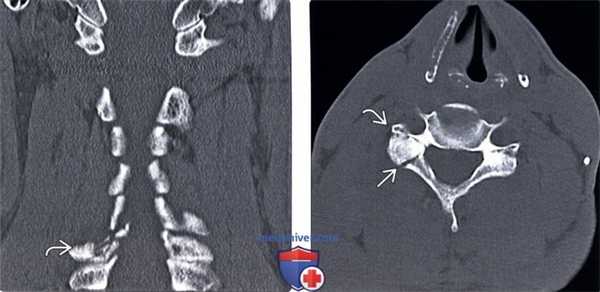

(Слева) На фронтальном КТ-срезе у пациента с гиперэкстензионно-ротационным повреждением шейного отдела позвоночника виден односторонний оскольчатый перелом правой суставной колонны С7 с незначительным смещением фрагментов.

(Справа) КТ, аксиальный срез: перелом правой суставной колонны и пластинки дуги С6, приводящий к травматической сепарации суставной колонны.